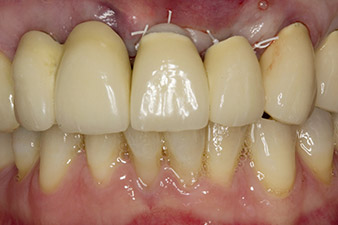

Une fois la cicatrisation primaire obtenue, les tissus mous ont été formés à l'aide du bridge doublé à la base. Deux mois plus tard, la zone a été exposée au moyen d'une incision de la crête alvéolaire légèrement orientée côté palatin (Fig 2). Les dimensions de l'os alvéolaire se sont avérées suffisantes en position 22. Les Figures 2 et 4 illustrent la préparation du lit implantaire, le taraudage et la pose de l'implant à l'aide de l'Implantmed.